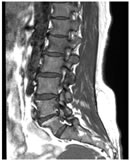

CASE 5

T1W AXIAL IMAGE SHOWING DIFFUSE DISC BULGE, LIGAMENTUM FLAVUM HYPERTROPHY AND BILATERAL FACETAL ARTHROPATHY CAUSING SEVERE THECAL SAC STENOSIS

T2W MID SAGITTAL IMAGE SHOWING MINIMAL RETROLISTHESIS OF L2 OVER L3 AND DISC DEGENERATION AT ALL LUMBER INTERVERTEBRAL LEVELS WITH REDUCED DISC HEIGHT AT FEW LEVELS. THERE IS DISC PROTRUSION NOTED AT L2-3, L3-4, L4-5 LEVELS CAUSING INDENTATION OVER THECAL SAC